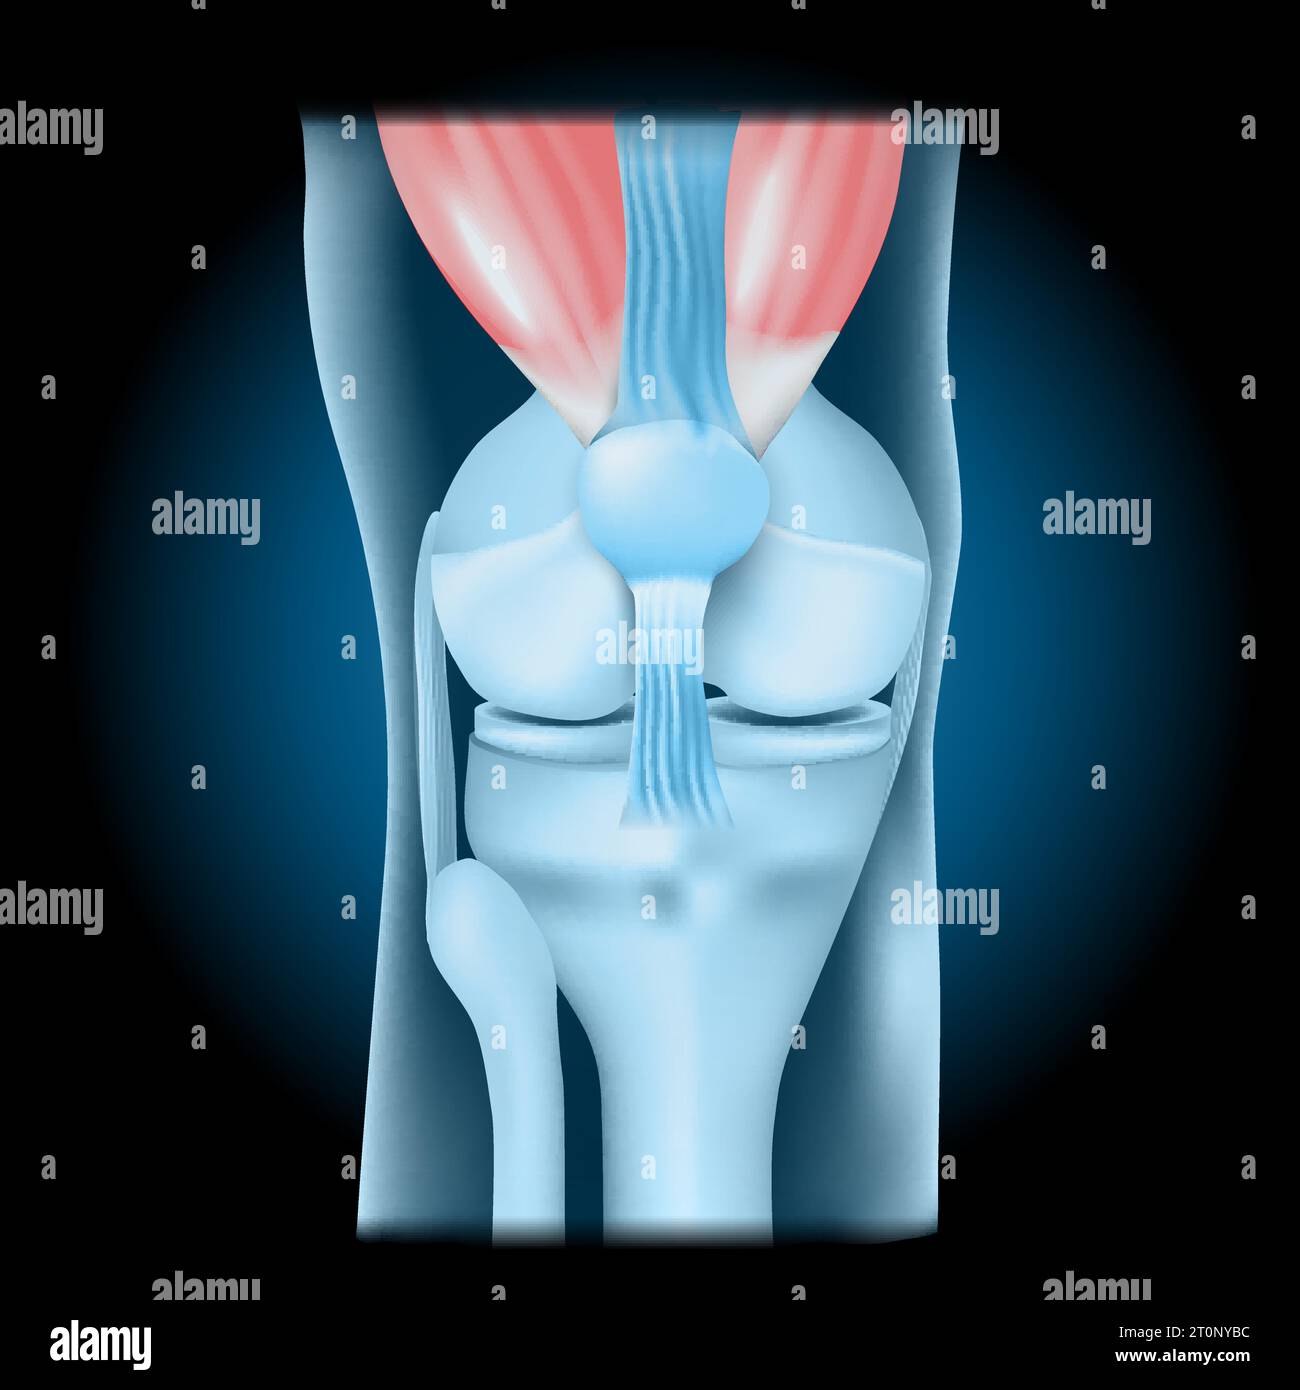

Articulation du genou avec quadriceps. Vue de face du genou humain avec effet lumineux. Joint bleu transparent réaliste sur fond sombre. illustration vectorielle lik Illustration de Vecteurhttps://www.alamyimages.fr/image-license-details/?v=1https://www.alamyimages.fr/articulation-du-genou-avec-quadriceps-vue-de-face-du-genou-humain-avec-effet-lumineux-joint-bleu-transparent-realiste-sur-fond-sombre-illustration-vectorielle-lik-image568424624.html

Articulation du genou avec quadriceps. Vue de face du genou humain avec effet lumineux. Joint bleu transparent réaliste sur fond sombre. illustration vectorielle lik Illustration de Vecteurhttps://www.alamyimages.fr/image-license-details/?v=1https://www.alamyimages.fr/articulation-du-genou-avec-quadriceps-vue-de-face-du-genou-humain-avec-effet-lumineux-joint-bleu-transparent-realiste-sur-fond-sombre-illustration-vectorielle-lik-image568424624.htmlRF2T0NYBC–Articulation du genou avec quadriceps. Vue de face du genou humain avec effet lumineux. Joint bleu transparent réaliste sur fond sombre. illustration vectorielle lik